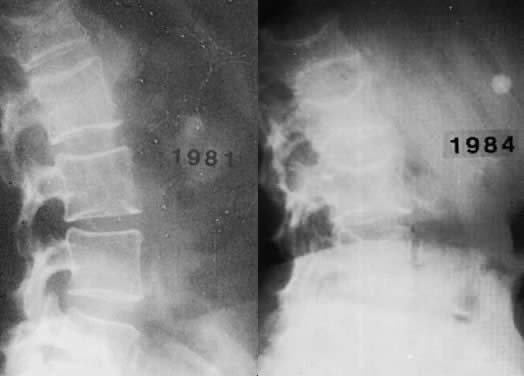

Osteoporosis is an insidious disease and often goes undetected until a painful compression fracture occurs. Only in hypoestrogenic female athletes and dancers may stress fractures be the first sign. Back pain is frequently the first complaint associated with osteoporosis; at first presentation, radiologic changes are usually not evident. A minimum of 25% to 30% of bone mineral content must be lost for osteoporosis to be diagnosed by routine radiographs (Fig. 3). Sudden severe pain may indicate vertebral collapse. The principal complications of osteoporosis include distal forearm fractures, vertebral compression fractures, and hip fractures. Distal forearm fractures (i.e. Colles' fractures) are the first to increase, with a 10-fold rise occurring in Caucasian women as they age from 35 to 60.

Fig. 3. Radiograph of the spine of a patient with postmenopausal (involutional) osteoporosis. A. At 51 years of age. B. At 54 years of age. The patient suffered two hip fractures in the intervening 3 years.

Spinal compression fractures, the most frequently occurring of the osteoporotic fractures, may cause pain, loss of height, and postural deformities. Such fractures are 10 times more common in white women than in men, occurring in 25% of Caucasian women over the age of 60. The average postmenopausal woman shrinks approximately 6.35 cm. Some loss of height is secondary to narrowing of the disc space. Small vertebral fractures are responsible for anterior collapse of the vertebral bodies, leading to dorsal kyphosis (i.e. dowager's hump).